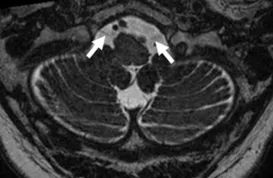

A Steady-state free precession (SSFP) axial image showing the glossopharyngeal and vagus nerves (circles).

A Steady-state free precession (SSFP) axial image showing the spinal accessory nerves (circles).

A Steady-state free precession (SSFP) axial image showing the hypoglossal nerves (arrows).